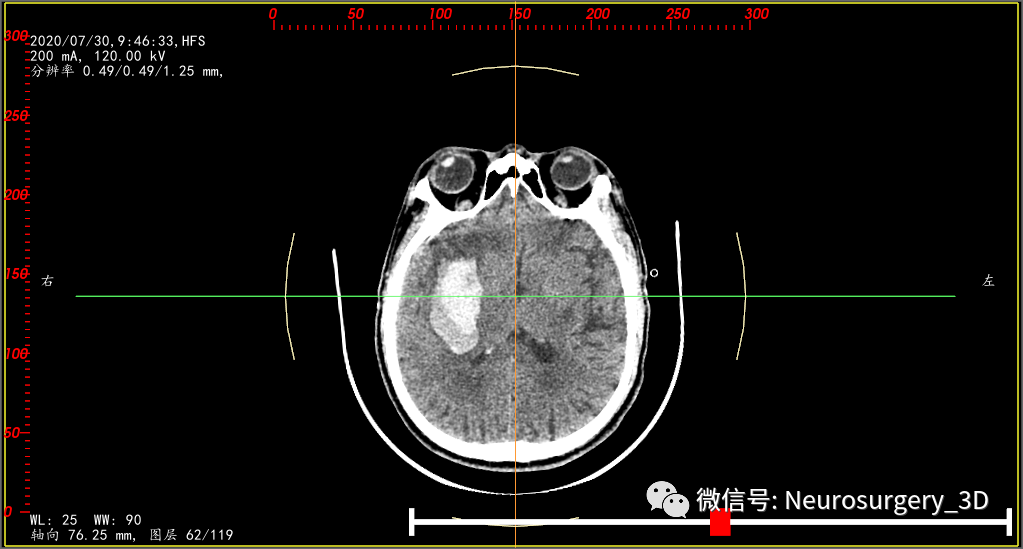

两天后的CT复查(2020年7月30日9:46)并测量不同区域的CT阈值,三维重建阈值选择45-100,包含低密度血肿区域。

是活动性出血吗?对比脑部活动性出血CT征象,一些文献报道:CT混杂征是由Li等在2015年提出的一种预测血肿扩大的影像标记,主要是指(1)血肿内存在边界分明的高低密度两种成分,(2)两种成分CT值至少相差18HU,且(3)低密度成分不包含于高密度成分中的一种征象。其形成的机制是血肿内凝固的血块在CT上呈现高密度,而低密度区域可能是由于破裂的血管仍在持续出血,血液尚未凝固所致。(下符CT混杂征片)

对比上述文献1、2、3还真像活动性出血,血肿较前两次CT检查又有增大现象,如果考虑活动性出血,手术方案无疑选择开瓣血肿清除了,年龄、身体耐术力、基础疾病等种种影响因素都是在活动性出血因素之后考虑的次要因素。

我中心近年来多次遇到这种CT征象:1、血肿内存在界限分明的高密度区域和低密度区域,且低密度区域呈半包围于高密度区域;2、多次CT复查,高密度血肿增加不明显,血肿扩大为低密度血肿;3、一般初次CT检查是高密度血肿,2-3天后血肿体积扩大,扩大的血肿为低密度血肿,高密度血肿无扩大。其形成机制考虑为长期饮酒或口服抗凝药物后,脑部小血管破裂出血致血肿凝固析出渗液,低密度血肿所含血清成分较多,为不凝液状态。这种形态血肿微创穿刺治疗血管比较理想,手术也证实,在微创手术中液态部分能较容易引出,起到迅速减压,缓解颅内压力的目的。

为了验证是不是活动性出血,再次复查颅脑CT(2020年7月30日15:10)如下:两次CT(间隔约6小时)对比,血肿形态无明显变化,证实并非活动性出血。